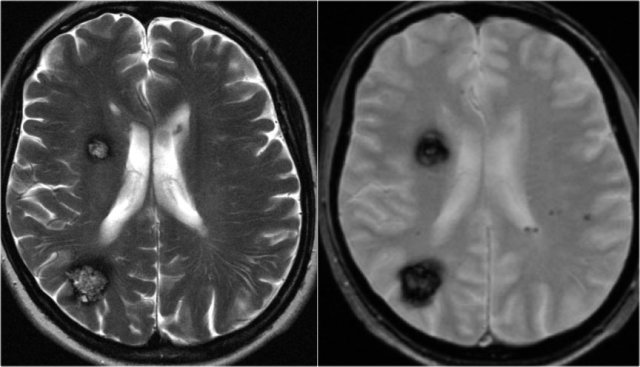

The images show typical focal cortical dysplasia.

There is cortical thickening and blurring of the grey/white matter junction on T1WI (left).

The FLAIR image on the right shows the subcortical hyperintensity.

The images demonstrate cortical and subcortical signal abnormalities on T2WI and FLAIR in the left temporal lobe indicating focal cortical dysplasia.

Notice associated T2/FLAIR hyperintense and shrunken hippocampus as a result of mesial temporal sclerosis, i.e. dual pathology.